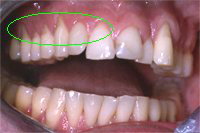

Ein 31 Jahre alter Patient zeigt einen starke Zahnfleisch-Rückgang im Oberkiefer (Abb. 1 und 3) und wir beschliessen, diese Rezessionen zu behandeln.

Der Erfolg der Behandlung ist deutlich in den Abb. 2 und 4 zu sehen. Sehr augenfällig konnte die Situation um den Eckzahn im linken Oberkiefer verbessert werden (vergleiche dazu Abb. 3 vorher und Abb. 4 nachher).